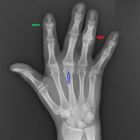

Препараты для лечения суставов — список лекарств